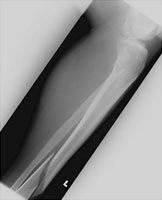

Fractures of the shaft of the tibia are due to direct trauma. This particular fracture is spiral in nature. More comminuted fractures of the proximal tibia may compromise blood supply of the popliteal artery, and angiography may be considered.

- Click on the image for a larger versionAAP radiograph of the tibia and fibula. There is a spiral fracture of the tibia.